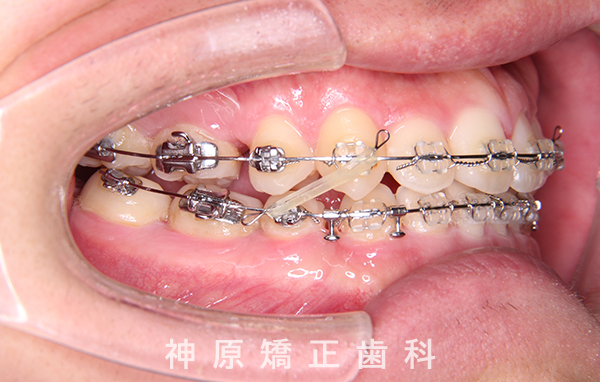

マルチブラケット装着1年後

精密検査の結果、大きな骨格的なずれはありませんでした。しかし、あごと歯の大きさのバランスが悪く、すべての歯を並べると横顔の見た目が悪化する可能性がありました。また、適切な歯軸の獲得も難しい状況でした。そのため、小臼歯を抜歯して適切なスペースを確保し、歯並びを整えることにしました。これにより、ガタガタした歯並びや前歯の噛み合わせの問題が改善されました。